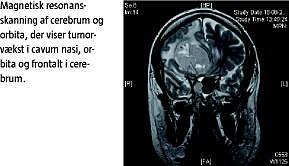

Sygehistorie